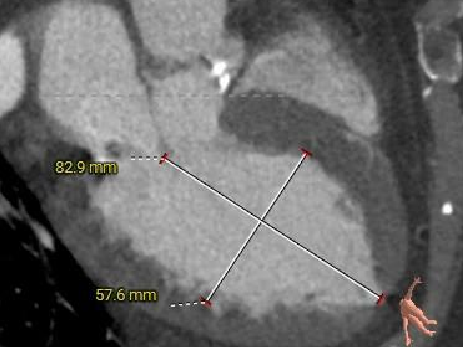

左室测量

外周入路评估